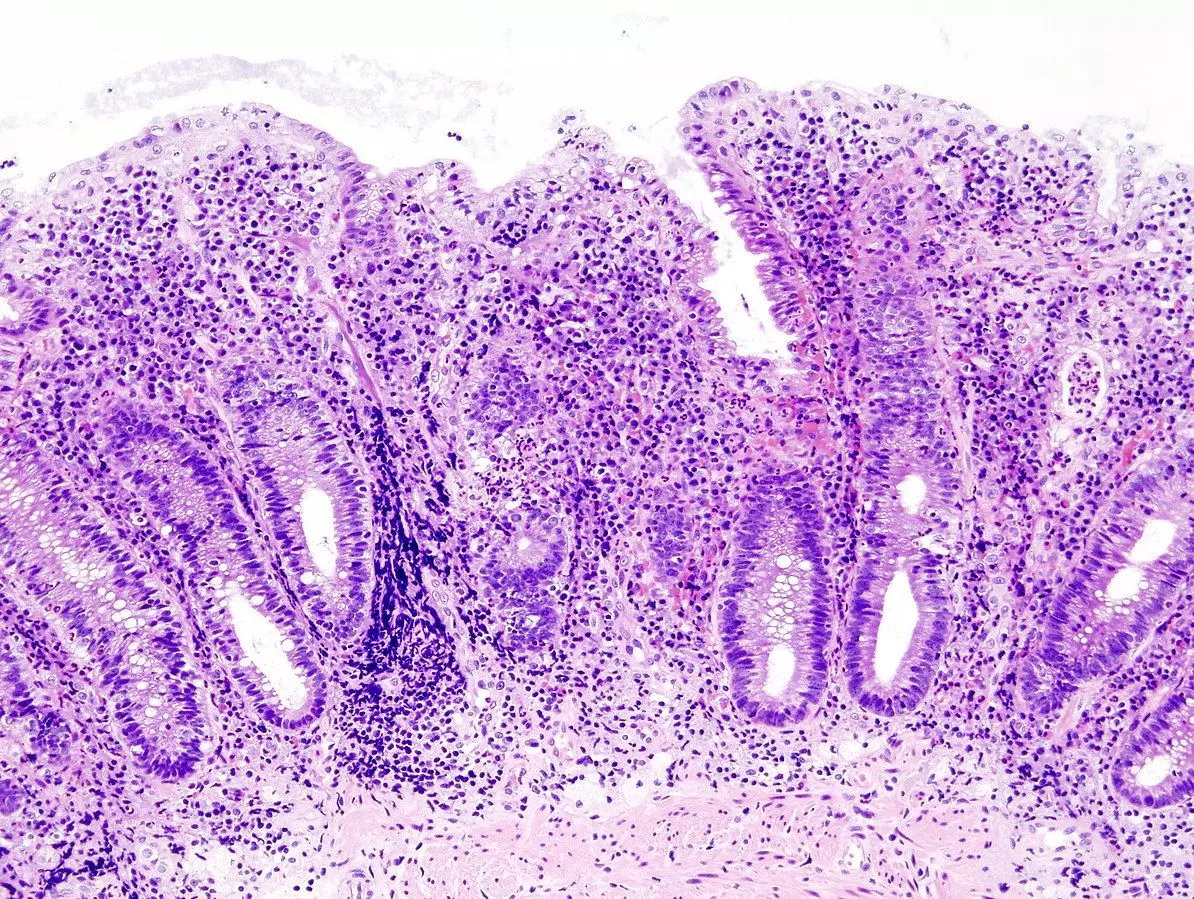

Image - Granuloma of Crohn’s disease

On colonoscopy, the gross pathological features that may be apparent are skip lesions (areas of normal bowel between two affected lesions), mucosal oedema, transmural inflammation, deep ulcers, cobblestone appearance and fistulae with the bladder/vagina/skin. If a tissue sample is taken, microscopy will show granulomas - collections of epithelioid macrophages.